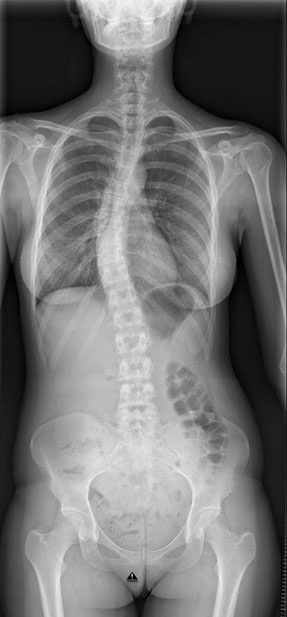

• Fehlhaltungen der Wirbelsäule (Skoliose)